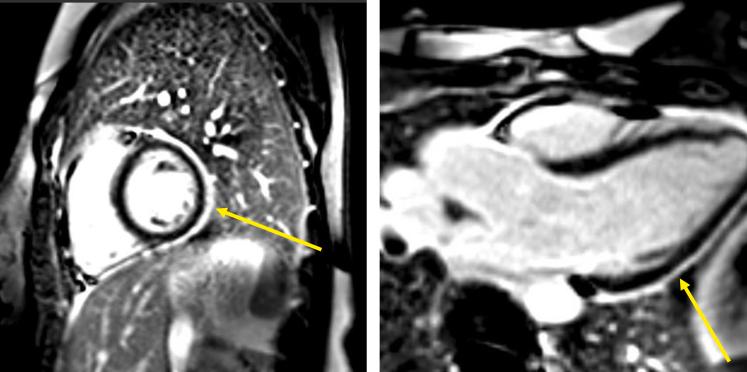

Complicated Pericarditis: Understanding Risk Factors and Pathophysiology to Inform Imaging and Treatment.

J Am Coll Cardiol. 2016 Nov 29;68(21):2311-2328. doi: 10.1016/j.jacc.2016.07.785.